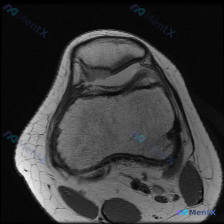

这是一张膝关节髌股关节层面的T1加权轴位MRI图像,核心问题是评估是否存在软骨异常,我们先看影像的客观发现:

- 骨骼结构:髌骨形态、骨皮质连续性正常,骨髓信号无异常局灶改变;股骨远端滑车部位关节面形态尚可,骨皮质连续,骨髓信号均匀

- 关节软骨:髌骨后方关节软骨和对应股骨滑车软骨厚度大致正常,表面光滑,未见明确剥脱或局灶性缺损

- 其他结构:髌股关节间隙可见少量T1低信号影,考虑为少量关节积液,无明显关节囊增厚或滑膜增生;皮下脂肪、股四头肌肌腱等周围软组织形态信号未见异常

- 排除红旗征象:未见明确肿瘤占位、骨髓炎、骨质破坏,也没有明显的重度髌股关节退行性改变(软骨磨损、软骨下骨囊变、骨赘)